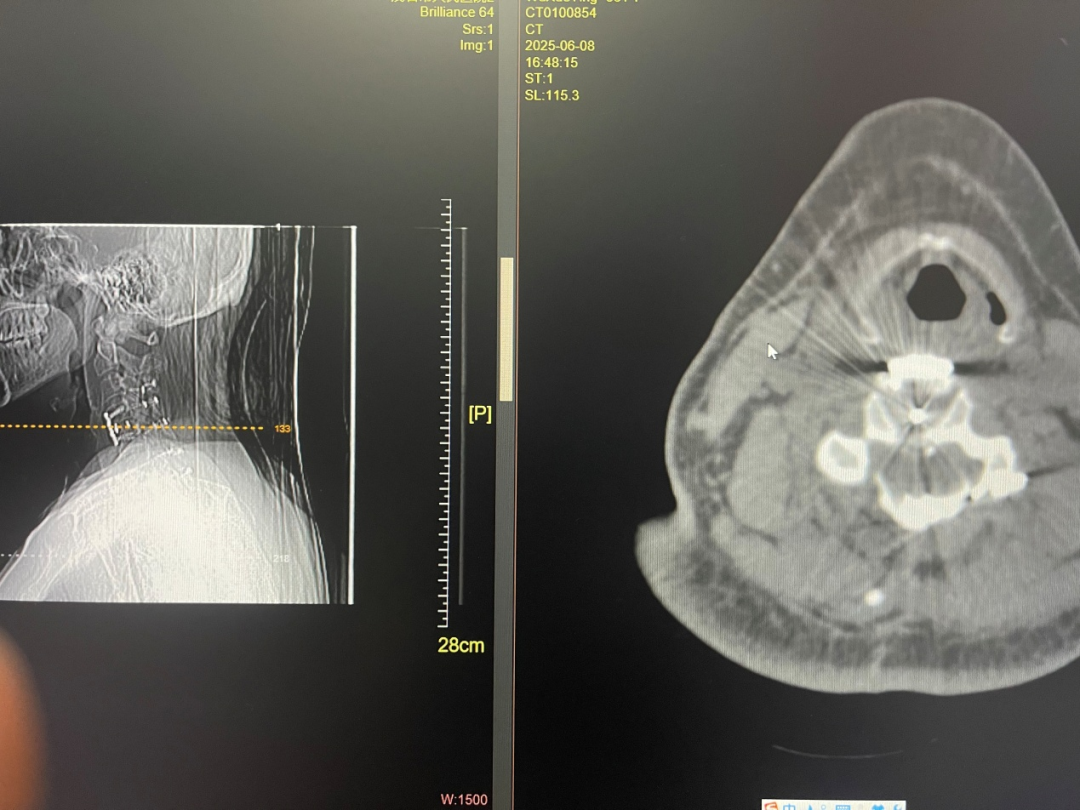

▲患者术后CT

术中,赵斌修发现,吴姨的脱出髓核虽然没有骨化,但脱出物较上一个病人更为巨大且与硬膜囊粘连严重。手术团队仔细抽丝剥茧,脱出的椎间盘组织绝大部分被取出,尚残余与硬膜粘连紧密的一薄层,此时硬膜已恢复搏动。考虑到此时若再继续清除这一薄层残余的粘连组织,有极大的可能会造成脊髓的损伤,手术团队经过斟酌后最终决定结束手术的减压步骤。